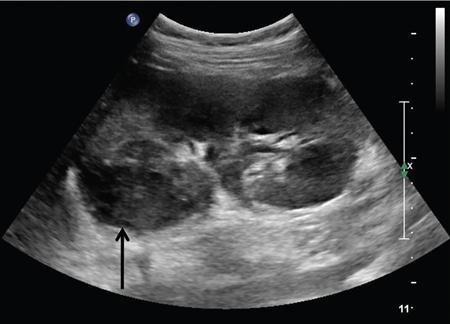

Anmol Bhatia, Ajay Prashanth Dsouza, Kushaljit Singh Sodhi Urinary tract infection (UTI) is a common cause of febrile illness in children, second only to respiratory tract infections. The incidence before 14 years of age ranges from 3%–10% in girls and 1%–3% in boys; however, the incidence is more in boys during infancy. The clinical spectrum in increasing order of severity ranges from asymptomatic bacteriuria and cystitis to acute pyelonephritis and septicemia. Urinary tract anomalies, prematurity, indwelling urinary catheters, lack of circumcision in boys and high-grade vesicoureteral reflux (VUR) are some of the common predisposing factors. Although the clinical outcome is good in most patients, a few may develop long-term complications like hypertension, chronic renal insufficiency and end-stage renal disease. Given the poor localizing signs and the dreaded complications, a high degree of clinical suspicion, prompt diagnosis and treatment and tailored follow-up play pivotal role in management of these patients. Urine culture is the most important tool to establish the diagnosis and identify the causal pathogen, Escherichia coli being the most commonly isolated bacteria. Midstream clean catch urine sample is used in toilet-trained children while the sample is often obtained by suprapubic aspiration or transurethral catheterization in younger age group. A colony count of >105 CFU/mL of a single species in a midstream clean catch sample is confirmatory. Although imaging can aid in the diagnosis of an ongoing UTI, the main role lies in identifying the associated urinary tract abnormalities and also to look for the extent of consequent renal insult. Some of the common anatomic abnormalities predisposing to recurrent and complicated infections include VUR, congenital pelviureteric junction (PUJ) obstruction, ureterocoele, posterior urethral valve, ureteral duplication and neurogenic bladder. The imaging modalities commonly used in children are ultrasound (US), which helps in detection of structural anomalies, hydroureteronephrosis, urinary tract stones and renal scars; voiding cystouretherography (VCUG) for detecting VUR and 99mTc-labelled dimercaptosuccinic acid (DMSA) scans to look for renal scars. US is often used as the first-line imaging modality because of its easy availability, low cost, non-invasiveness and lack of ionizing radiation. UTI, when confined to the lower genitourinary tract, frequently called as cystitis, reveals diffuse bladder wall thickening (Fig. 10.8.1A) with hazy margins on grey-scale US, which may show increased vascularity on Doppler (Fig. 10.8.1B). Floating echoes in the urine are commonly seen. The distal ureter may also be dilated and show mural thickening. Since UTI confined to bladder is mostly uncomplicated, it does not usually warrant a further imaging workup. However, in cases of severe bladder trabeculations, unilateral gaping ureteral ostium, open bladder neck, follow-up for bladder outlet obstruction, dysfunction or VUR may be indicated after the acute infection settles. Inflammatory response to the infection leads to swelling and decreased perfusion in renal parenchyma. Findings on intravenous urography (IVU) include renal enlargement, a diffuse or patchy striated nephrogram with delayed opacification and effacement of pelvicalyceal system. On renal US, diffuse or localized renal enlargement may be the only finding. Other typical findings include altered parenchymal echotexture, usually hypoechoic (Fig. 10.8.2) but may be hyperechoic, along with poor corticomedullary differentiation. Colour or power Doppler study reveals reduced vascularity. On 99mTc DMSA or glucoheptonate scans, photopenic defects due to reduced accumulation of renal cortical tracers are seen. The defects may be solitary, multiple or may involve the entire kidney giving a mottled appearance. DMSA renal scintigraphy with a sensitivity of 99.9% is the imaging modailty of choice for diagnosing acute pyelonephritis (APN). Among the patients with UTI, 50%–91% show defects on nuclear scans, suggestive of acute pyelonephritis. When both VUR and APN are present, scintigraphy is abnormal in 79%–86% of children. Permanent scars are known to occur in 38%–57% of children diagnosed with APN on nuclear scan, not withstanding the grade of VUR. 99mTc DMSA scan is the imaging modality of choice for detection of renal scars and they also appear as photopenic defects; however, the temporal course of study helps to differentiate it from APN. Thus, follow-up scanning at 3–6 months may be suggested to detect if the kidney has healed or scarred. CECT reveals striated nephrogram along with multiple wedge-shaped or round hypoenhancing areas with apices directed towards calyces (Fig. 10.8.3). Perinephric fat stranding may also be seen. MRI reveals wedge-shaped or round, T2 hyperintense lesions with decreased signal on inversion recovery sequences. And similar to CECT, striated nephrogram and inflammatory changes in perinephric fat may be demonstrated. MRI can also help in detection of renal scars. Despite it being a radiation-free modality with utility in poor renal function, MRI is less often used due to limited availability, higher cost, longer scan times and need for prolonged sedation. Acute focal bacterial nephritis is a localized or segmental form of acute pyelonephritis, also known as acute lobar nephronia, usually affecting only a renal pole or one moiety in a duplex kidney. It appears as an ill-defined, poorly marginated mass in contrast to renal abscess which is relatively well-defined, surrounded by enhancing walls (Fig. 10.8.4). The mass is usually hypoechoic on USG with low-level internal echoes and shows reduced vascularity on Doppler. CECT shows ill-defined or wedge-shaped hypodense areas which correspond to focal photopenic defects on nuclear scans.